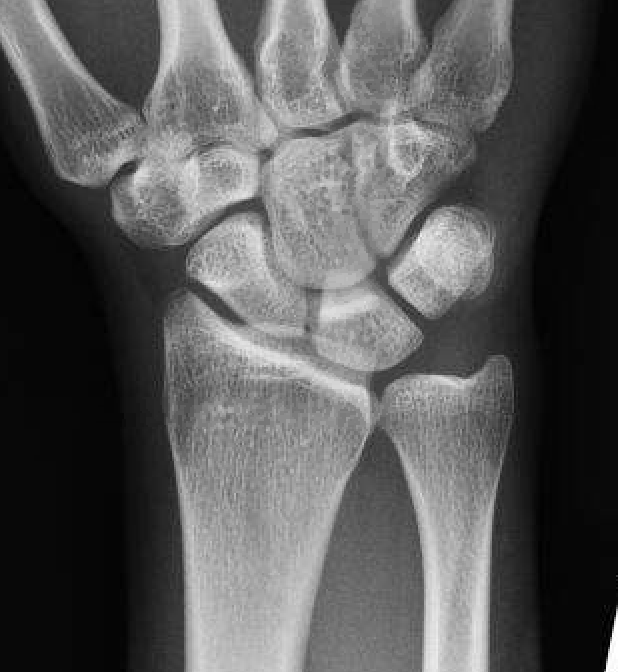

Ulna variance

Supination and pronation alter variance

- varies up to 3 mm with wrist position

- pronation increases ulnar variance

- supination decreases variance

90 / 90 view

- zero rotation view

- neutral supination / pronation

- PA film with wrist in neutral

- elbow 90° / shoulder abducted 90°

Line from lunate fossa and ulna head

- wide variation in population

- mean ulna variance is 1 mm (range 2 - 4)

Ulna neutral

Ulna positive

Ulna negative